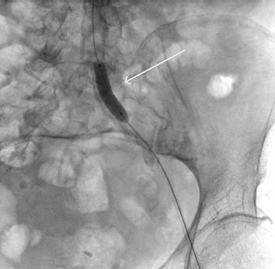

В ходе операции выполнен разрез по линии Кена в верхней трети левого бедра. Выделены ОБА, ПБА и ГАБ. В ОБА пальпировалась циркулярная атеросклеротическая бляшка. Была выполнена продольная артериотомия ОБА c переходом на устье ГАБ. Выполнена эндартерэктомия из ОБА. Решено произвести профундопластику заплатой для расширения устья ГАБ. В качестве пластического материала использован участок ствола большой подкожной вены, резецированный из этого же доступа и реверсированный. Пластика аутовенозной заплатой нитью 6/0. Пуск кровотока. В участок передней стенки ОБА выше места заплаты был установлен интродьюсер 7 фр. (рис. 2). При ангиографии визуализирована окклюзия ОПА на протяжении. После проведения мягкого гидрофильного проводника установлен баллон со стентом Balton Neptun 10 на 60 мм, выполнена ангиопластика и стентирование ОПА (рис. 3 и 4). На контрольной ангиографии восстановление просвета ОПА (рис. 5). Зафиксировано появление четкой пульсации артерий в ране. В месте доступа наложен боковой шов на ОБА. Послойные швы на рану до активного дренажа. Кровопотеря за время операции до 100 мл.

Рис. 3. Имплантация стента на баллоне в окклюзированной ОПА (обозначено стрелкой)

Примечание: составлен авторами по результатам данного исследования

Рис. 4. Баллон сдут, стент имплантирован корректно (обозначено стрелкой)